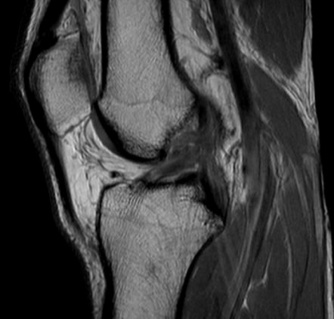

Knee MRI scan

MRI is a common technique for objectively diagnosing an ACL tear. Second place has been given to this assessment technique because MRI findings are not helpful in ruling in or ruling out knee instability. This is primarily due to the fact that diagnosis is made while the patient remains in a single position making it impossible to see the tibia's behaviour compared to the femur.

In addition, time is also needed after an ACL injury as the swelling present in the knee makes it difficult to diagnose the state of the ACL. This problematic is the result of the blood surrounding the ACL.

However, it should still be noted that ACL injury management is critically dependent on accurate diagnosis of other surrounding ligamentous structures of the knee, in particular the lateral collateral ligament (LCL), the posterior cruciate ligament (PCL) and the meniscus. These structures can indeed be assessed using MRI scans, which still makes this technique of evaluation highly worthy of application in the management of patients suffering form ACL injuries.

Patients with combined LCL/ACL or PCL/ACL tears indeed show profound instabilities requiring a more technical surgical procedure, which, if not taken into consideration predisposes the ACL graft to higher chances of collapsing.